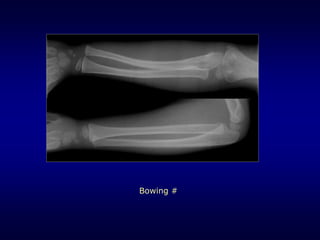

Bowing #